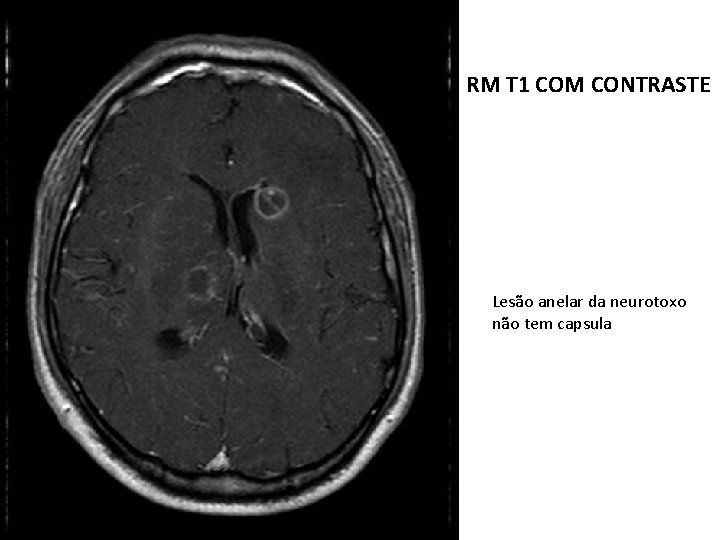

RM T 1 COM CONTRASTE Lesão anelar da neurotoxo não tem capsula

Toxoplasmose no SNC em pacientes imunocomprometidos: Sinais e sintomas de toxo aguda envolvem principlamente o SNC; Encefalite necrosante é causada por invasão direta do parasito; Necrópsia destes pacientes têm demonstrado o acometimento em múltiplos órgãos, e não apenas no SNC; Cometimento do SNC na toxo se dá no parênquima cerebral e não nas meninges;

Toxoplasmose A grande maioria dos pequenos vasos intracorticais mostram proliferação e reduplicação das camadas, não sendo possível distinguir entre média e íntima. Na vasculite os microrganismos parasitam as células endoteliais, que morrem, sendo substituídas por outras. No processo há espessamento da parede, produção de várias camadas de membrana basal e fibras reticulínicas com conseqüente redução ou oclusão da luz. A obliteração vascular generalizada leva a necrose coagulativa. Habitualmente, a necrose isquêmica do cérebro é liqüefativa, como no infarto.